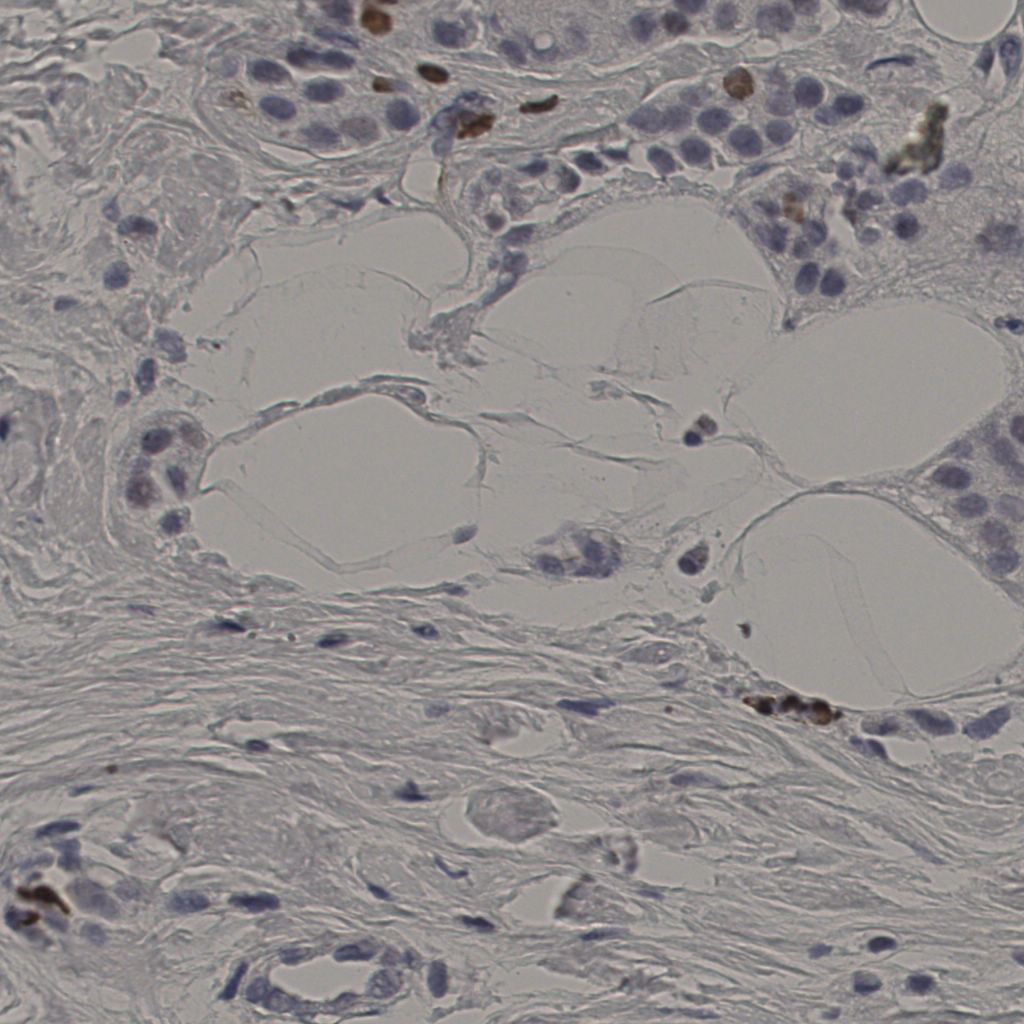

5.31%

Ki67 指数

阴 19502

阳 1093

切片统计

总切片

2970

有效

554

已标记

有效率

19%

标记后

标记前